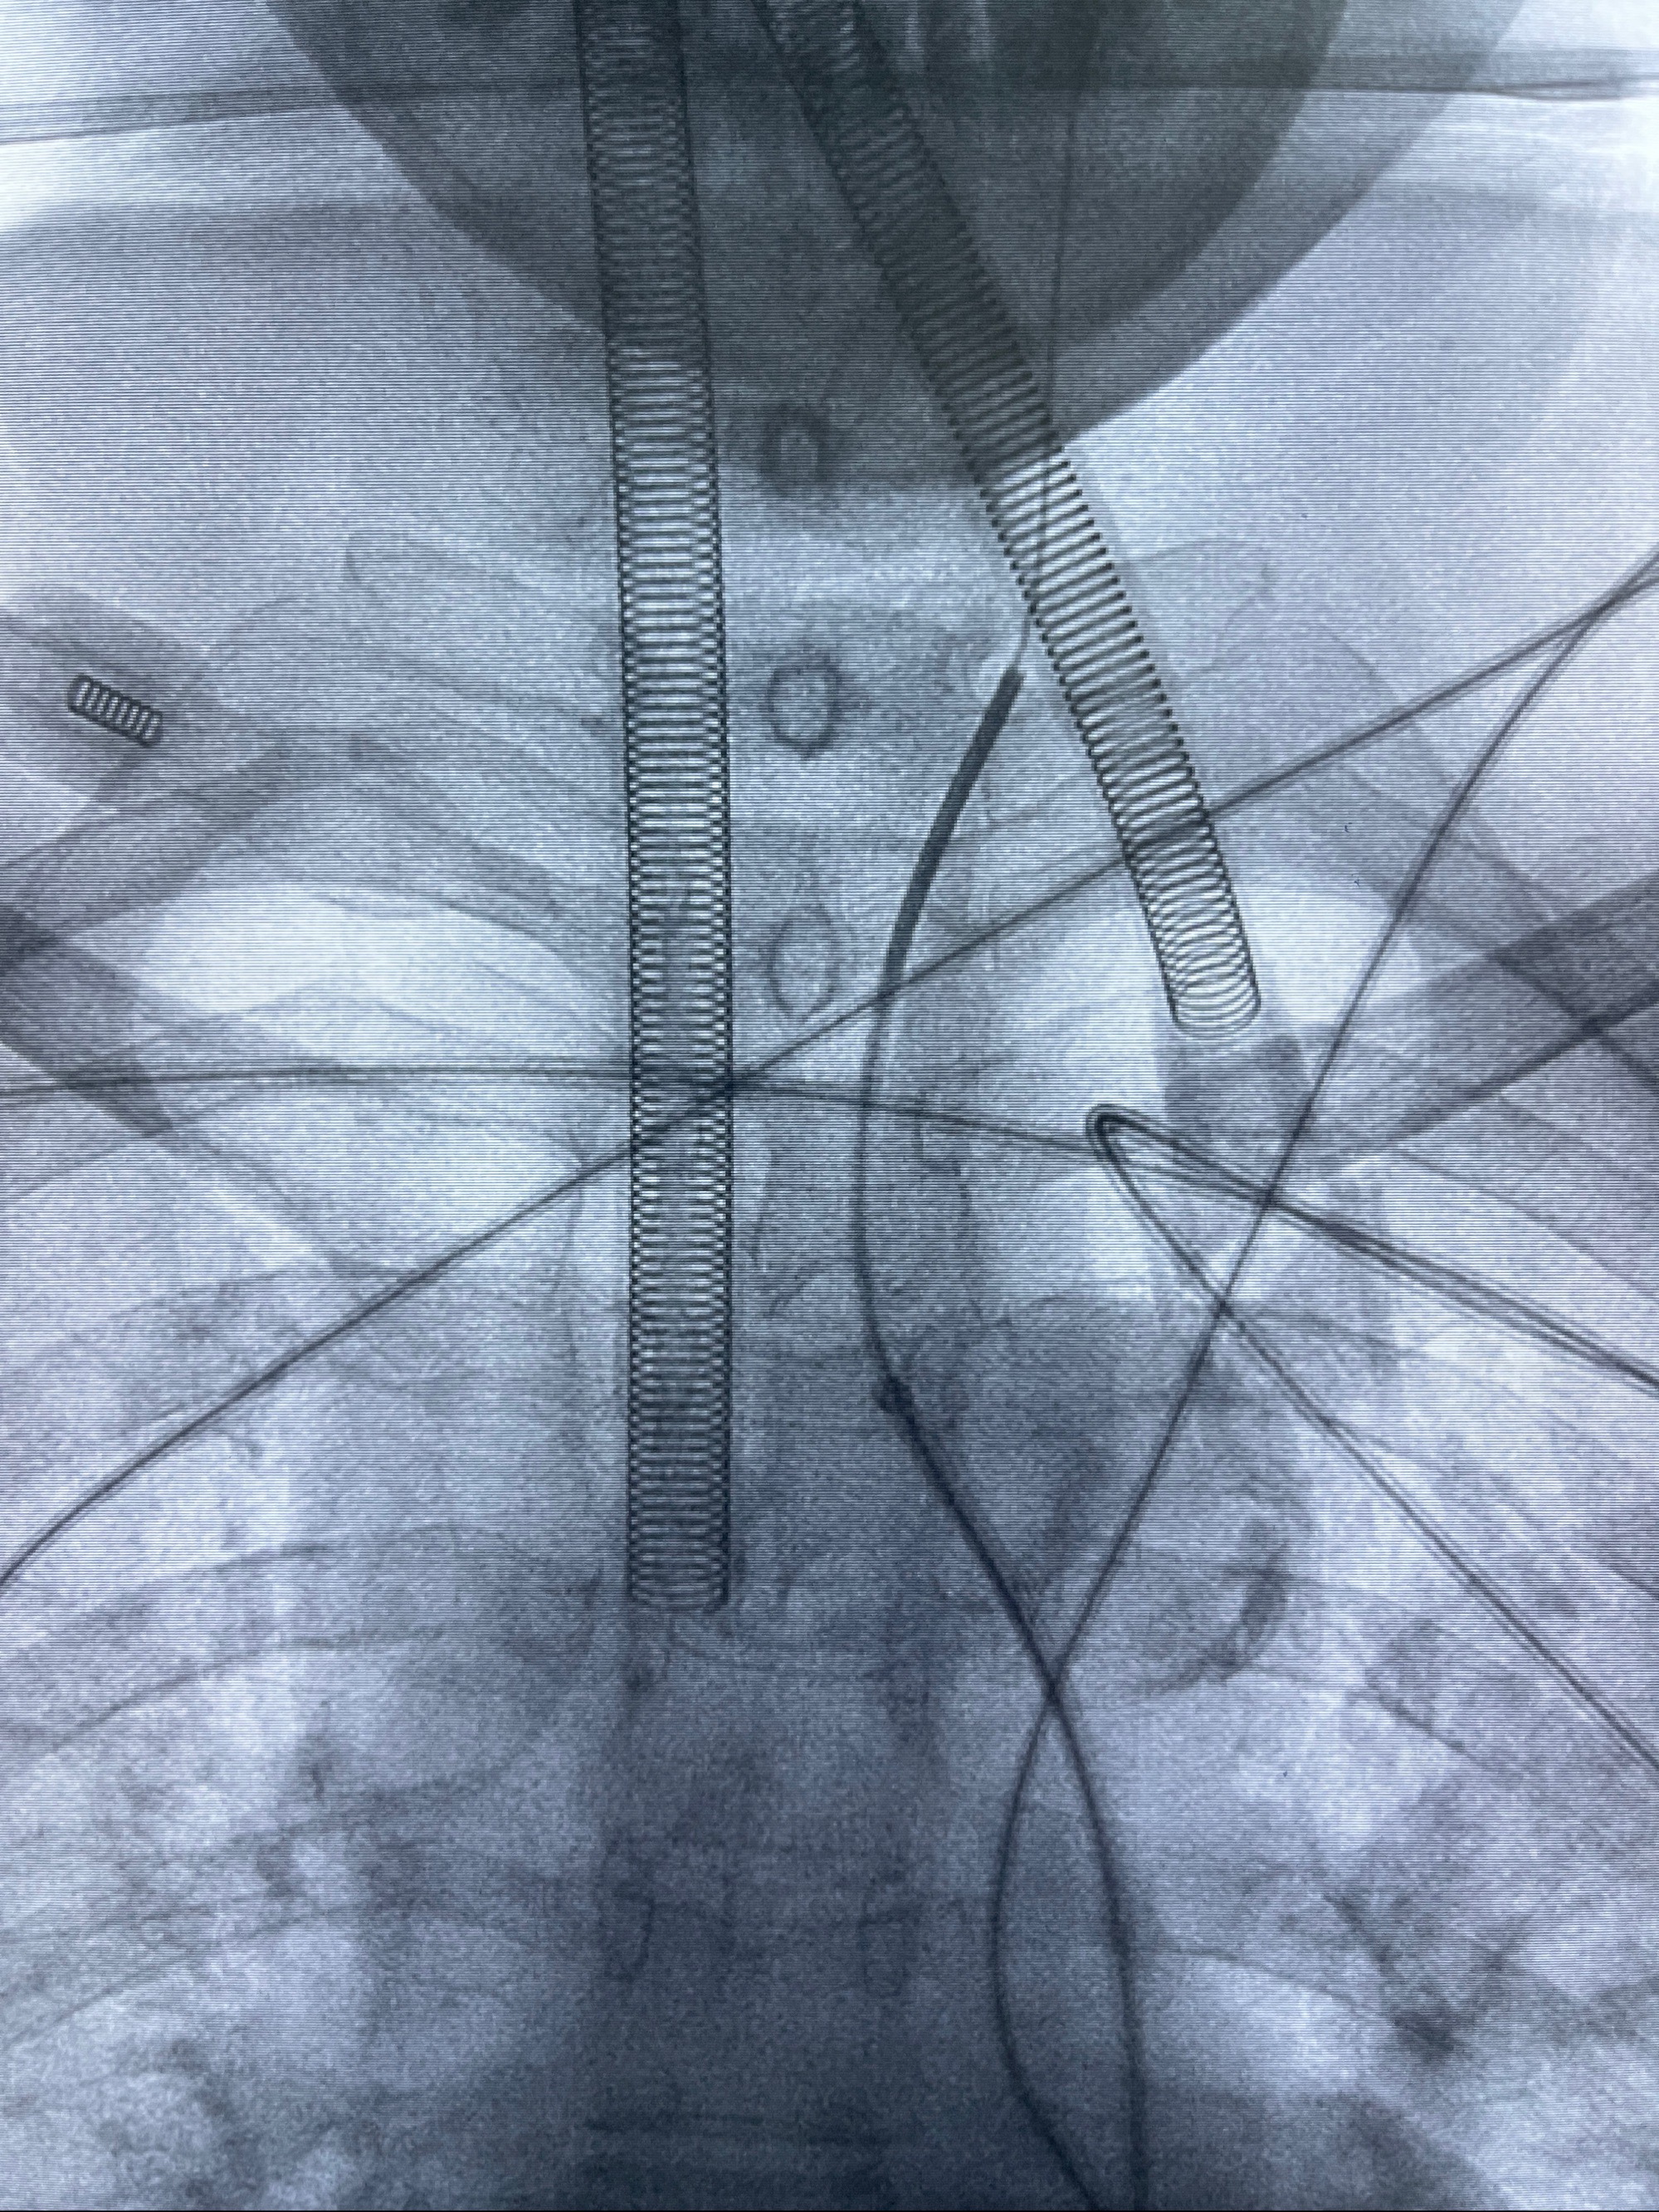

2023-09-06全麻下行左侧颈眼动脉瘤

密网支架辅助栓塞

- 普微森088 90cm导引导管

- 125cmMPA

- 0.035泥鳅导丝

- TB支架导管

- Echelon10 45°角微导管

- Synchro2微导丝

- Tubridge 4.0-20mm密网支架

- 加奇微弹簧圈:7*30/6*20/5*20/2*8